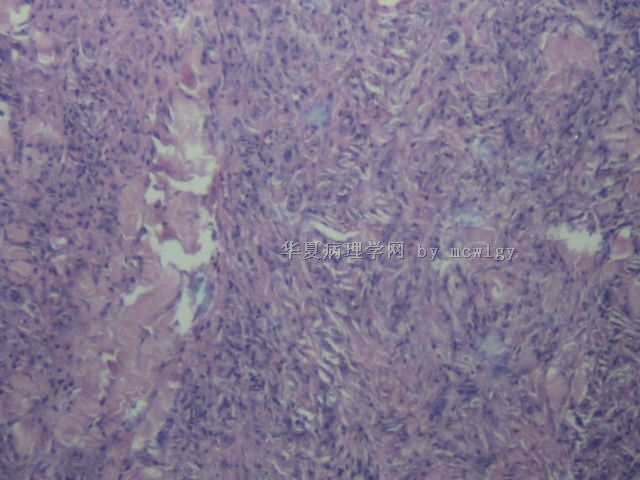

姓    名: ××× 性别:  男 年龄:  42

简要病史:  发现无痛肿物10天。

肉眼检查:  不整形3.5*3.5*2.5CM,红褐色,切面灰黄红褐色,质中.

结节性筋膜炎。

结节性筋膜炎

结节性筋膜炎又称假肉瘤性筋膜炎,发病原因不明,可能与外伤 或感染有关。该病有两个最重要的临床表现:一是迅速生长的肿块,通常在12周出现小肿块结节,病变处伴有疼痛、麻木或感觉异常;二是肿块通常较小,一般不超过2厘米,且病变有自限性。 本病易误诊为恶性纤维组织细胞瘤、纤维肉瘤、黏液性脂肪肉瘤等。美国有资料表明,结节性筋膜炎误诊率高达50%,过度诊断为恶

性的达20%。由于结节性筋膜炎是一种非肿瘤性病变,临床治疗主要

为局限手术切除,复发率低

重要病理改变

a 发生于筋膜,并侵至皮下组织,

b 限局性成纤维细胞及粘液样变性,病变中有血管增生及淋巴细胞浸润。

一般病理改变

a 病变中主要为大量成纤维细胞增生,伴有粘液样变性及多少不等的纤维增生,

b 胞核增大、深染 ,可有核丝分裂相,也可见多核巨细胞、软骨细胞、骨样组织,c 毛细血管增生,内皮细胞可增大、深染,

d 病变累及的周围组织常侵入筋膜或肌肉间隙,

e 病变边缘偶见炎细胞。